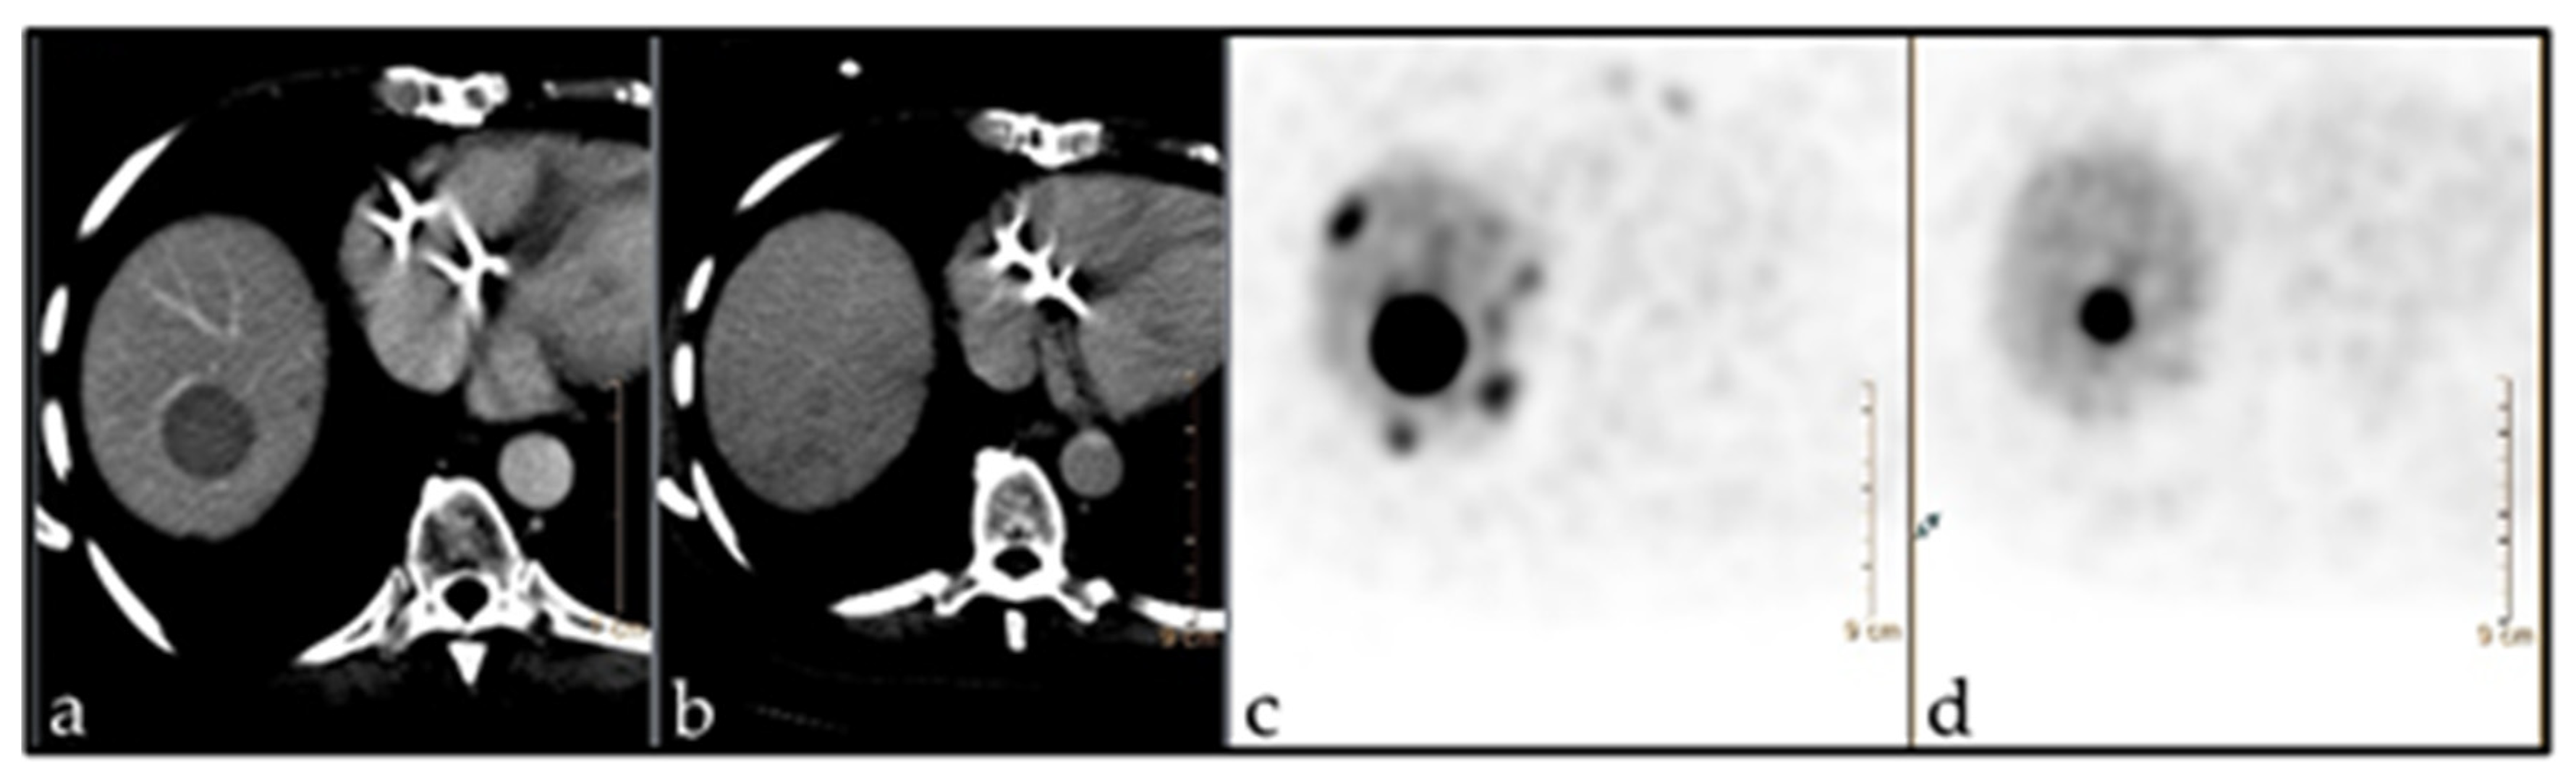

3.5. Pseudoprogression